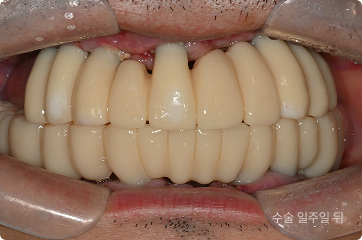

60세, 남 ㅣ중요한 일정 전

“딸이 곧 결혼하는데 그 전에 빨리 치료를 끝내고 싶어요.”

치료 전

원데이 임플란트

치료 후

• 6개월 후 딸의 결혼식 등 중요한 일정 앞둔 상태

• 의식하진정(수면마취) 하 전체 발치,

임플란트 수술 후 원데이 예비 치아 장착

• 발치 , 임플란트 식립 > 최종 보철

약 4개월 내 완성